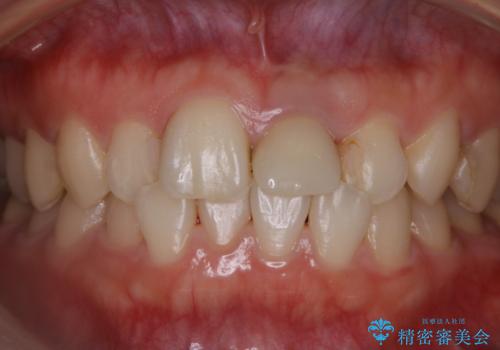

インビザラインのアタッチメントをつける前にPMTC

- インビザラインでの矯正治療中で、アタッチメントの設定前にきれな状態にしたいとのことでした。PMTC30分コースを行いました。

マウスピース矯正インビザライン治療では、歯の表面にアタッチメントという突起を設定します。(アタッチメントは歯の動きを効率的に移動するためのものです)

アタッチメントの設定時に、プラークや歯石・着色がついていると精密に付かないことや、外れやすくなることがあります。

PMTCを行い、専門的な機械でしっかりと汚れを除去してからアタッチメントの設定をすることがおススメです。